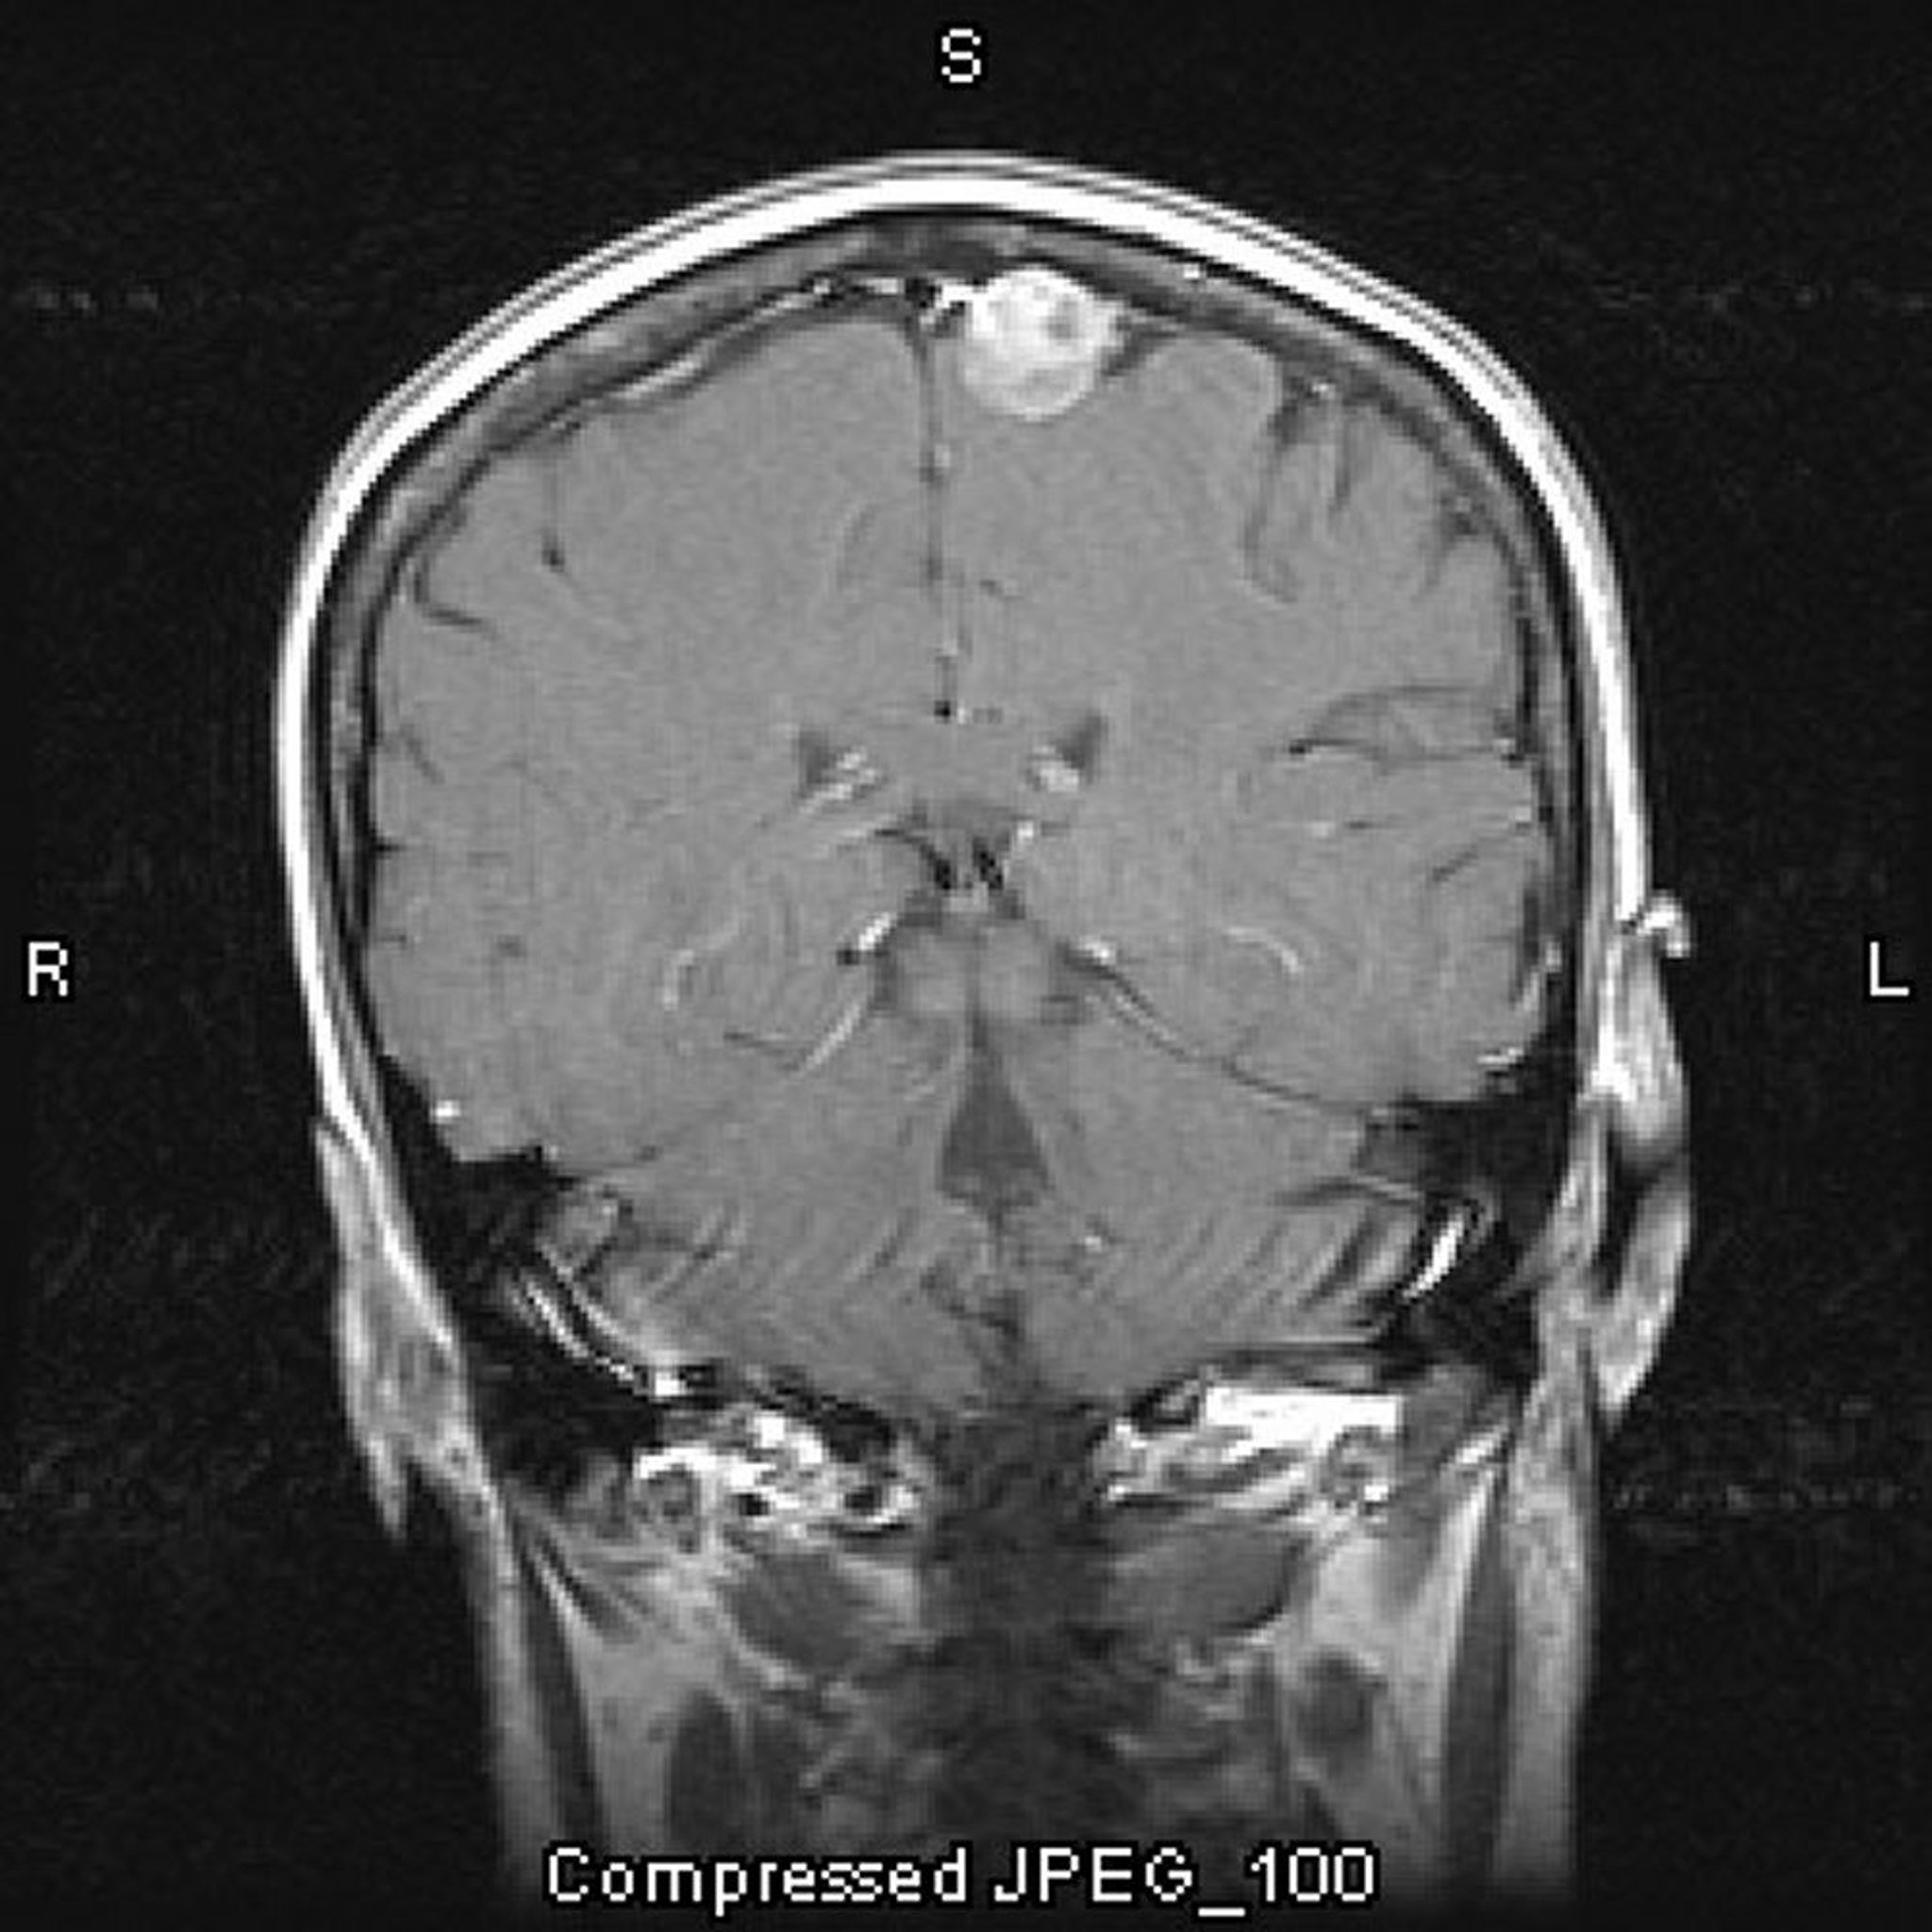

Менингиома (парасагиттальная)

На этом снимке МРТ с контрастированием показана менингиома. Парасагиттальное расположение является типичным для менингиом.

Image courtesy of William R. Shapiro, MD.